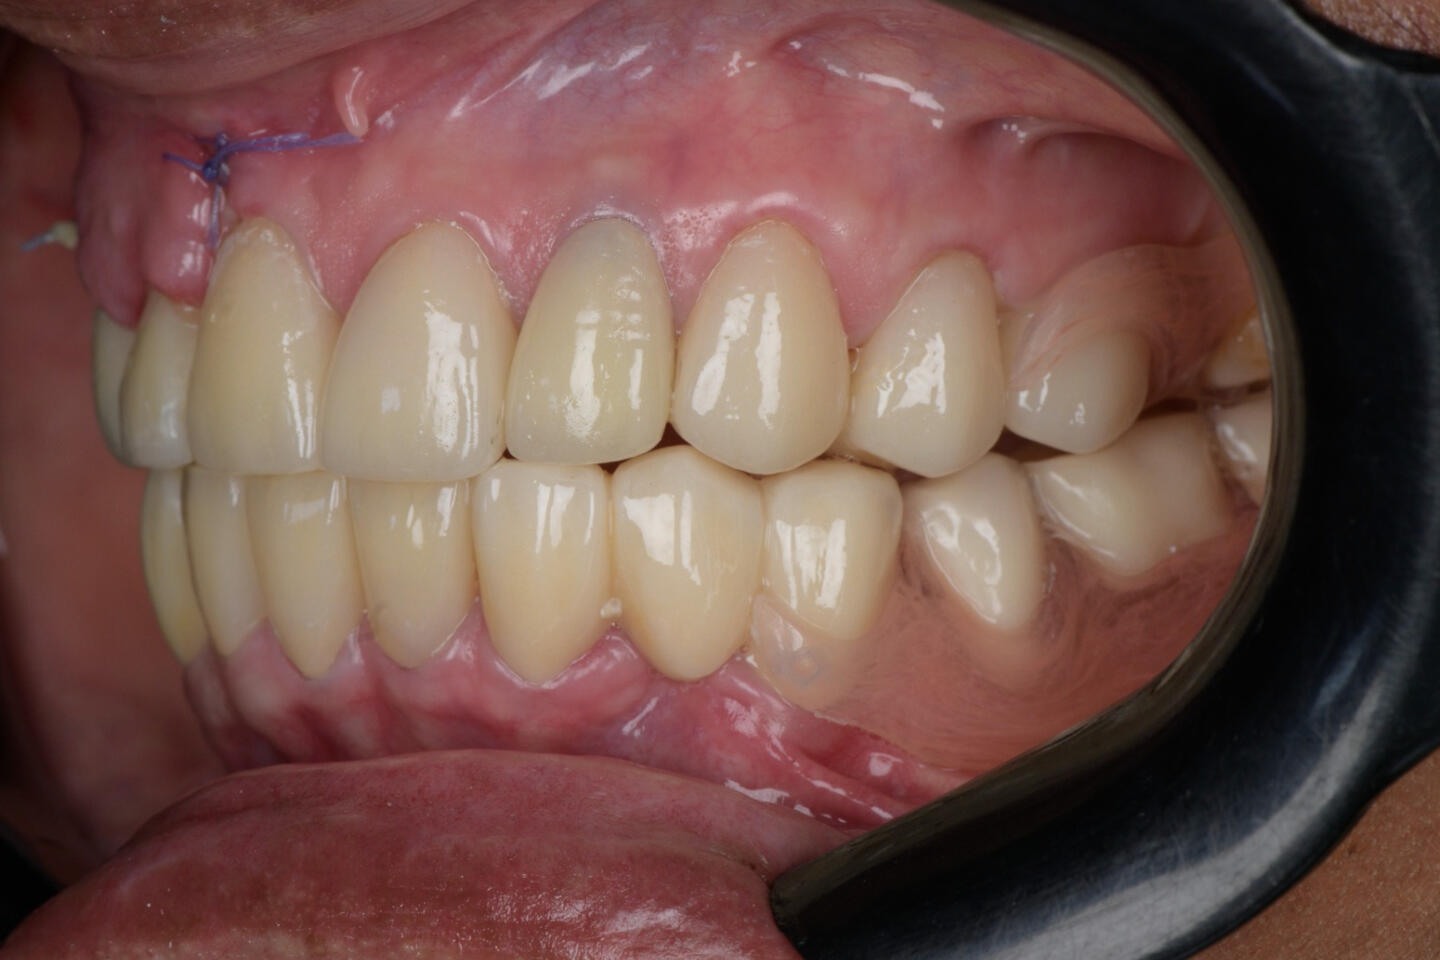

Complex Prosthetic Rehabilitation in an International Patient with Prosthetic Failure and Periodontal ComplicationsA patient from the state of Georgia (United States) sought specialized dental treatment due to complex failure of existing fixed dental prostheses. Clinical examination revealed prosthetic fractures, gingival inflammation, food impaction, compromised periodontal support tissues, and disruption of the smile line and occlusal harmony.A comprehensive prosthetic and periodontal treatment protocol was implemented, focusing on biological compatibility, functional occlusion, periodontal stabilization, and esthetic reintegration. Advanced restorative techniques and biomaterials were utilized to ensure long-term functional and biological stability.Post-treatment outcomes demonstrated improved periodontal health, occlusal function, and esthetic balance of the smile.This international case reflects transnational recognition of clinical expertise and highlights the importance of high-level interdisciplinary restorative and periodontal rehabilitation in complex prosthetic failures.